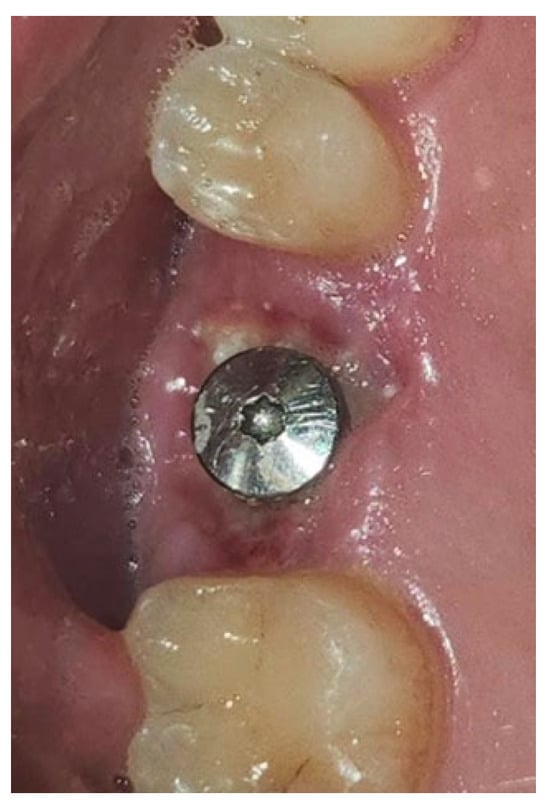

A similar technique was used in a 45-year-old patient with controlled hypertension, treated for the extraction of tooth 1.6 (Figure 11) and subsequent post-extraction implant-prosthetic rehabilitation (Figure 12). The surgical site was treated with bone graft material (Bio-Oss®—Geistlich), and a small amount of Glubran II was applied (Figure 13). Once again, Glubran II proved to be highly effective in stabilizing the graft material at the surgical site, providing excellent hemostasis and strong mechanical resistance from the film formed after polymerization (Figure 14).

One week after surgery, no signs of inflammation or suppuration were observed at the site. New tissue formation was noted within the rehabilitated site (Figure 15). The patient reported no discomfort related to Glubran II use, and bleeding was controlled during the surgery, thus reducing the risks associated with the patient’s hypertensive condition.

Figure 14. Surgical site after the complete polymerization of Glubran II.

Figure 15. Surgical site one week after surgery.